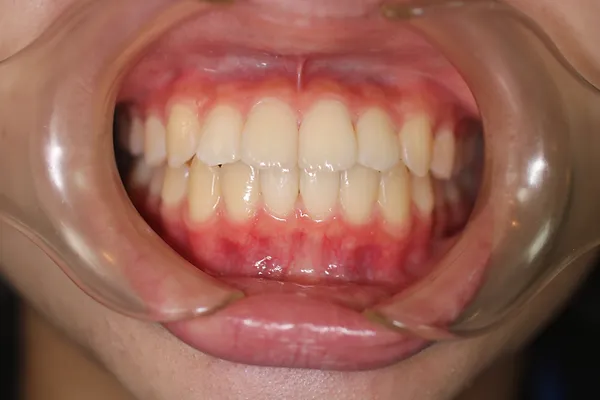

1矯正・マウスピース【治療例3】

治療前